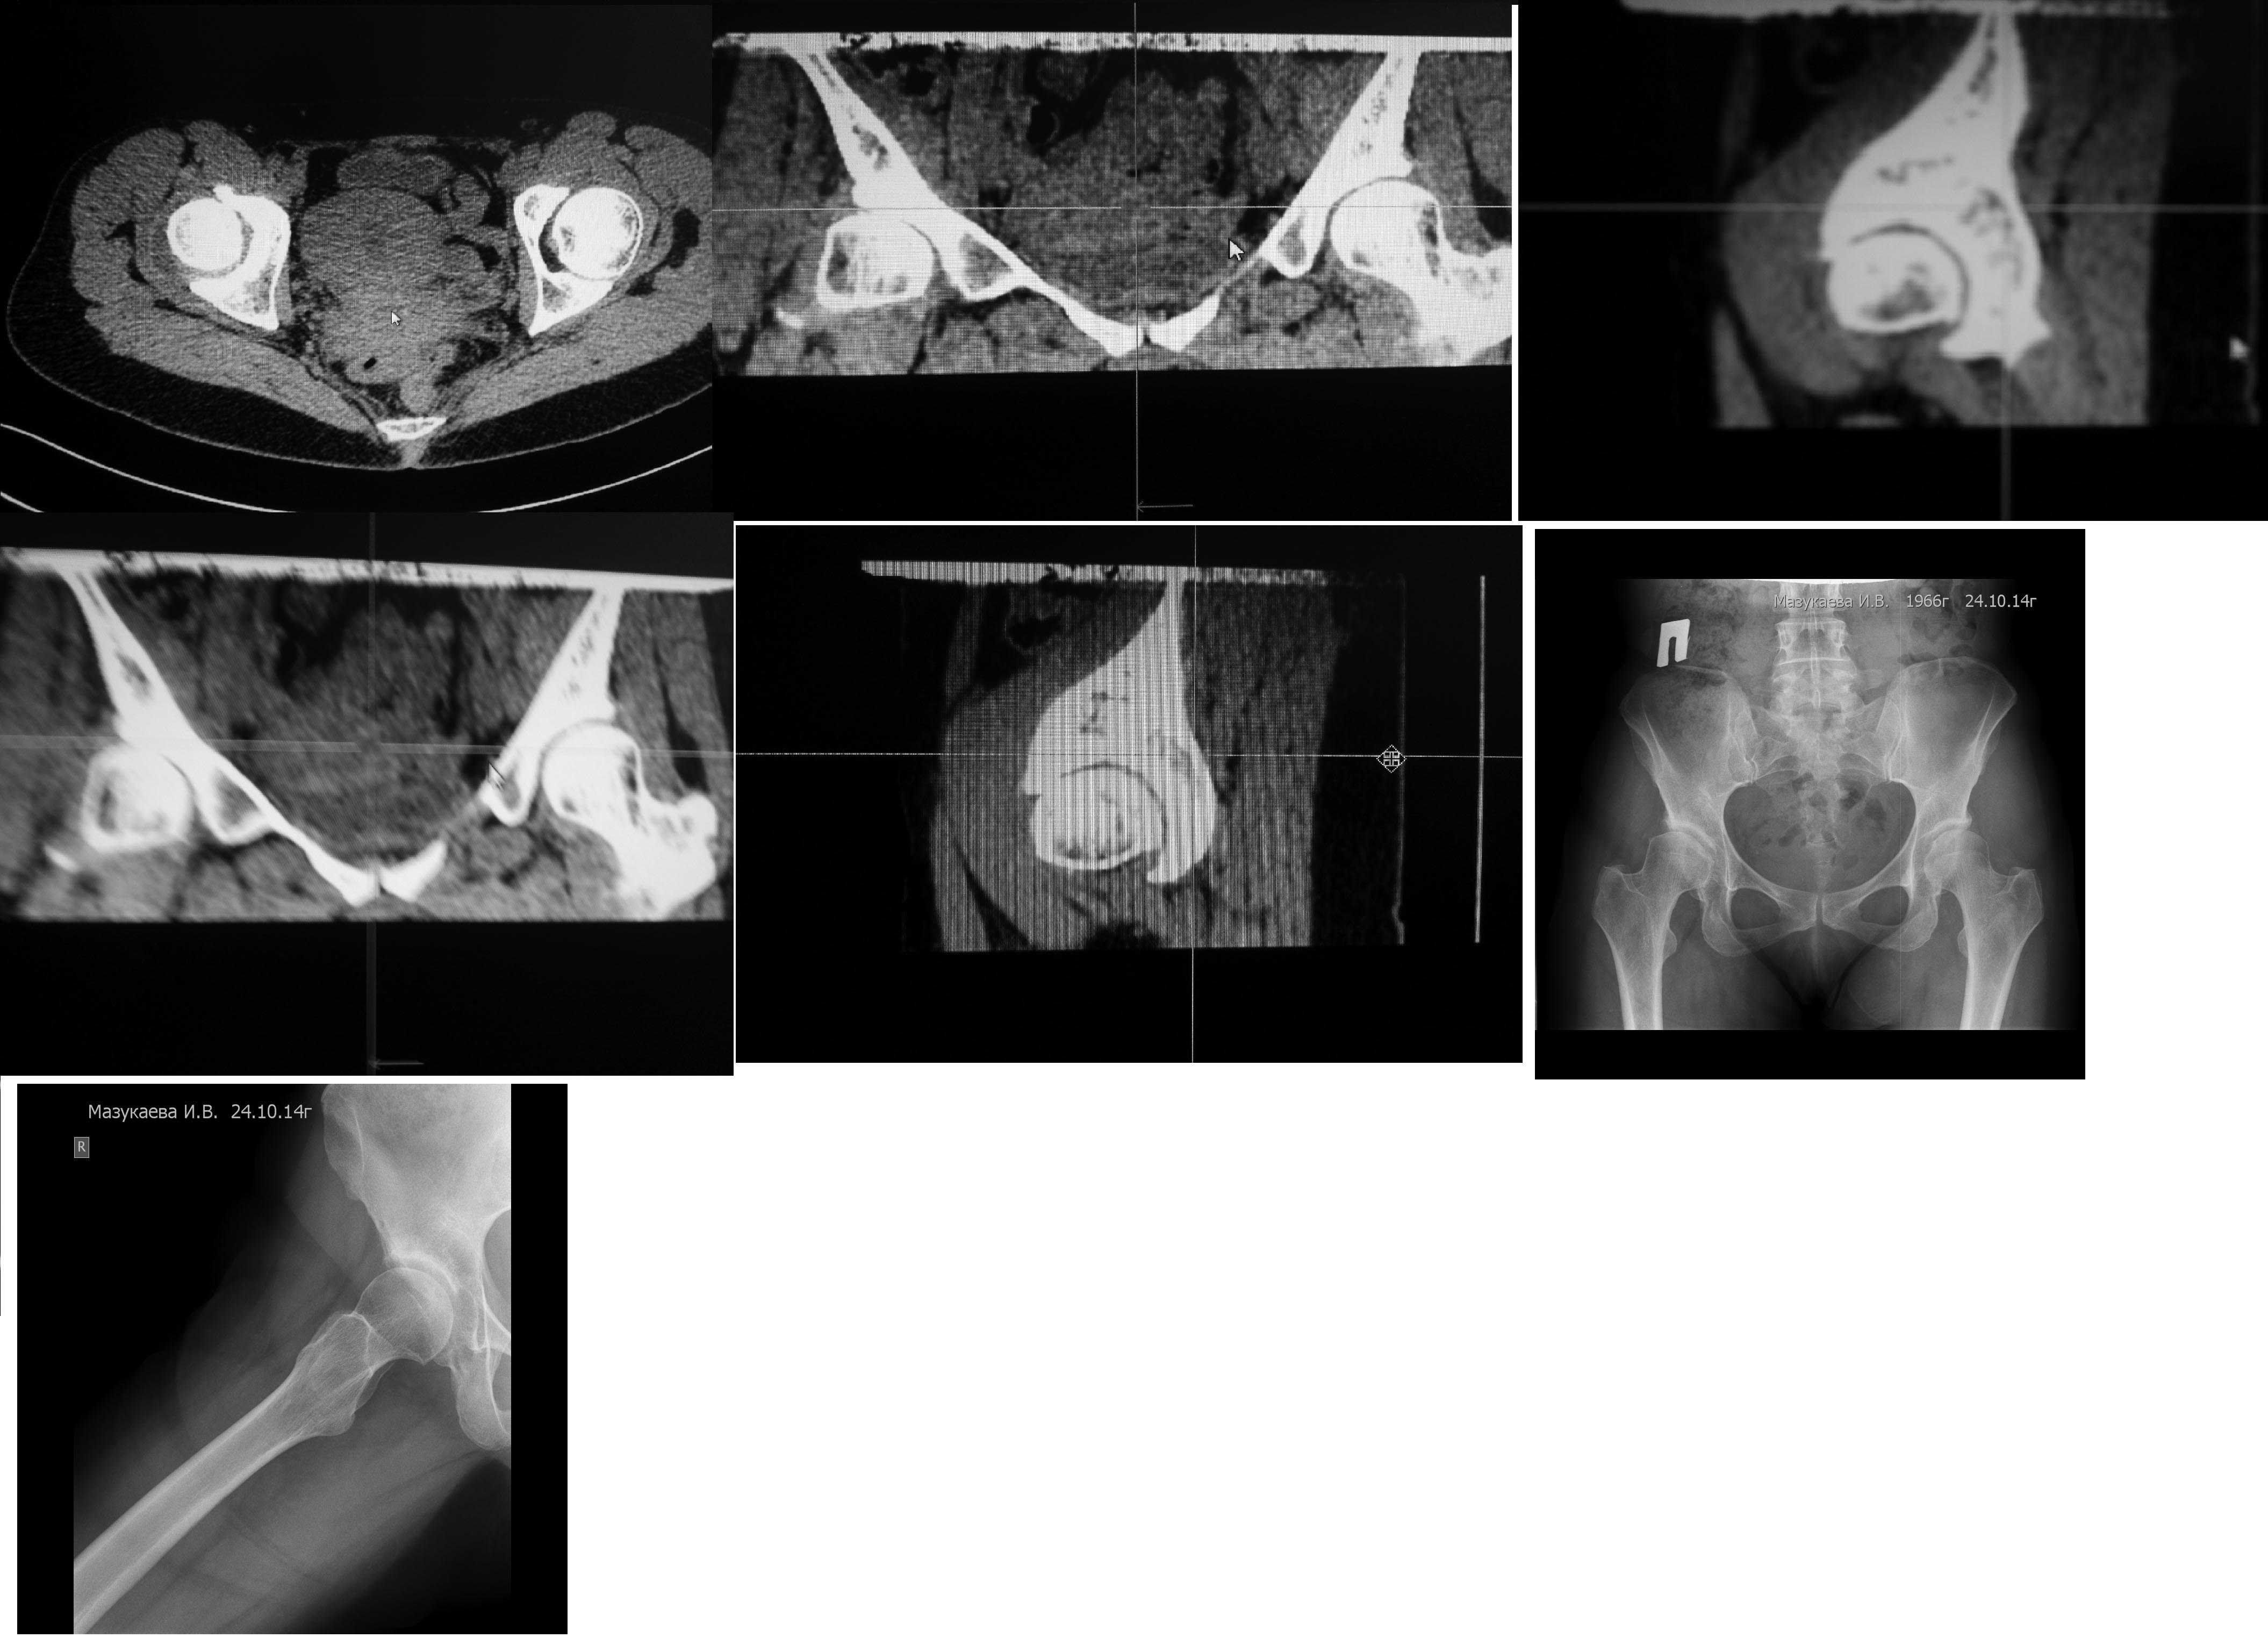

Уважаемый Андрей, представленных КТ-данных абсолютно не достаточно для диагностики ФАИ. Диагностику мы подробно расписали в недавно вышедшем 1-м томе Руководства. Необходимо иметь обзорные снимки таза, аксиальную проекцию, по Дану ну и КТ (МРТ), но не одного среза.

Для определения Hip Impingement недостаточно одного среза КТ. Более наглядно покажет прямой снимок таза, а МРТ вовлечение лабрума.

На прямом снимке таза можно определить показания к операции, и более приемлемым хирургическим доступом является flip trochanteric osteotomy, что позволяет без риска удалить импинжмент.

Это все, что есть!

тут дисплазия и импинджемент больше cam type, на мой взгляд. Одного лечения импинджемента будет недостаточно, придется делать и периацетабулярную остеотомию - а это хирургия класса hi-end. В 48 лет не стал бы заморачиваться. Недавно запротезировал пациентку с очень похожей картинкой, долго ломал голову, но пациентка была из очереди на ВМТ и настаивала на протезе. Головка интраоперационно выглядела неважно.

Андрей, доброго Вам вечера. Боюсь что речь идет не о ФАИ, а о банальном диспластическом коксартрозе у женщины 48 лет. Думаю что ПАО делать уже поздно, поэтому если есть выраженный болевой с-м, ограничение движений, больная принимает НПВП, то надо думать об эндопротезировании тазобедренного сустава